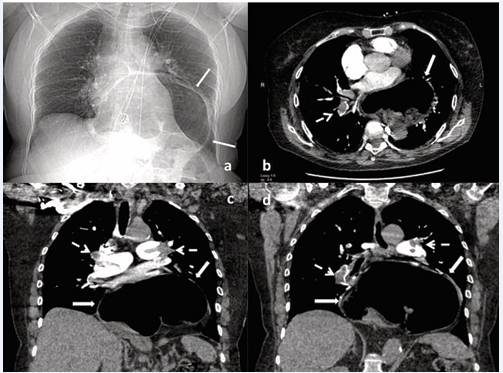

76 years-old woman, with a medical history of thyroidectomy and no significant medical history of thromboembolic disease, presented to emergency department with severe dyspnea and chest pain. Her respiratory rate was 38 breaths/min, blood pressure was 65/44mmHgand pulse rate was 118 beats/min. Chest X-Ray showed a mediastinum enlarged with a paracardiac lucency indicative of air-filled hiatal hernia (Figure 1a).

Figure 1 a) Admission chest X-Ray showing a mediastinum enlarged with a para-cardiac lucency indicative of air-filled hiatal hernia (arrows).

b,c,d) CT chest showing dilated right heart cavities, a large paraesophageal hernia into the thoracic cavity with complete herniation of the stomach (arrows) compressing the heart and blood vessels and defects suggestive of blood clots in the right and left branches of the pulmonary arteries (stippled arrows).

The computed tomographic scan of the chest revealed a large paraesophageal hernia with mass effect on the heart and pulmonary arteries and bilateral proximal pulmonary thrombi (Figure 1 b,c,d). The patient was treated with thrombolytic therapy and heparin. Venous ultrasonography showed no deep venous system thrombosis. The work-ups looking for neoplasia and for thrombophilia, turned out for inherited hypercoagulable disorders, were negative. A laparoscopic approach with reduction of the hernia contents into the abdominal cavity, diaphragmatic hernia repair and To upset fundoplication was performed 3 weeks after thrombolysis. Postoperative recovery was uneventful.